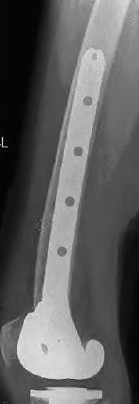

A 72-year-old male presents 2 years status post fixation of an impending pathologic right femur fracture due to metastatic renal cell carcinoma. He is minimally ambulatory due to pain. Despite radiation therapy, there has been progression of the lesion with extensive cortical bone loss, which is shown in Figure A. A proximal femoral replacement arthroplasty is performed without complications, and is demonstrated in Figure B. Which of the following is true regarding this patients post-operative course?

Deep prosthetic infection is the most common complication after hip arthroplasty performed for salvage of failed internal fixation after pathologic proximal femoral fracture secondary to malignancy.

Jacofsky et al reviewed the complications in 42 patients with a mean age of 63 who were treated with hip arthroplasty for salvage of failed treatment of a pathologic proximal femoral fracture. Multiple different constructs were used.

The most common complication was deep prosthetic infection, which occurred in nearly 10% of the patients studied. All infections occured in patients whom had previously received radiation. The mean Harris Hip score improved from 42 to 83 points post-operatively, and 41 of the 42 patients were ambulatory at follow-up. Implant survivorship free of revision for any reason at 5 years was 90%, and free of revision for aseptic failure or radiographic failure was 97%.

Figure A shows a lytic lesion of the proximal femur with an intramedullary implant. Figure B shows a proximal femoral replacement.